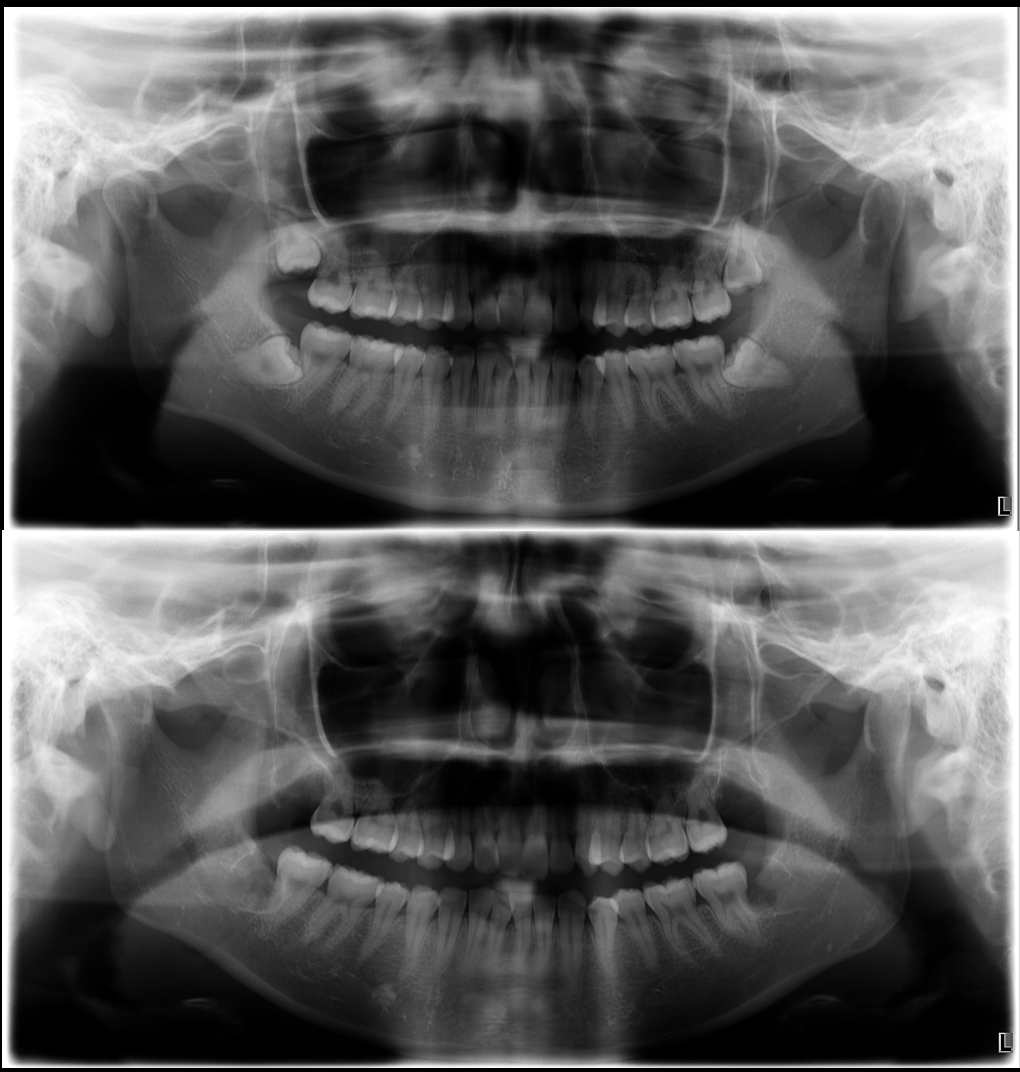

池袋でインナーブリーチ|前歯の神経を失った歯の...